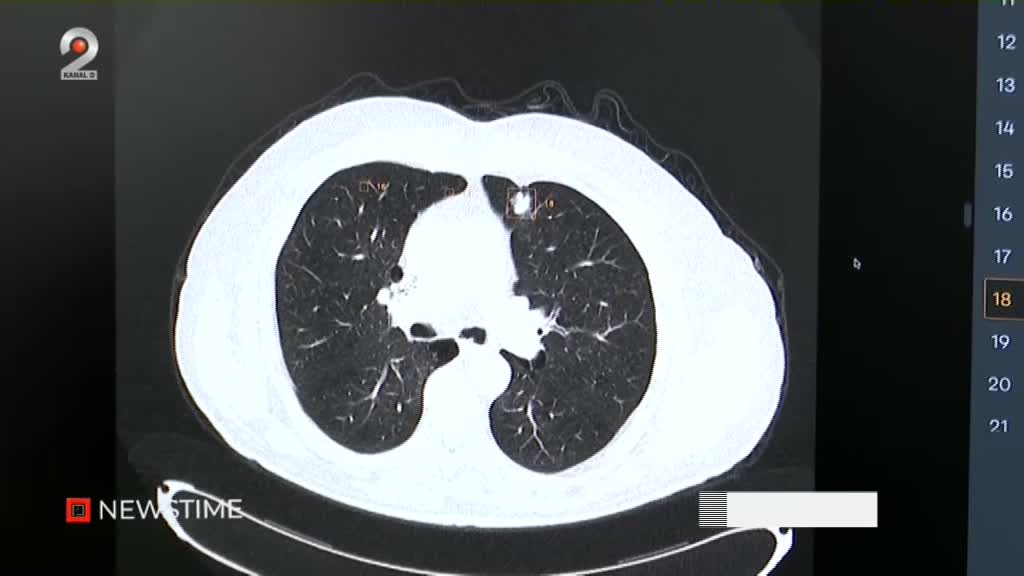

„Viitorii 10 ani în economie o să fie despre inteligență artificială”, a declarat Nicușor Dana, subliniind importanța stimulării celor care activează în acest domeniu, inclusiv prin reforme în sistemul educațional. Șeful statului a fost impresionat de procesul de dezvoltare al unei companii locale, care utilizează peste 100 de milioane de imagini medicale pentru antrenarea unui soft ce interpretează automat radiografii și

tomografii computerizate (CT).

Softul dezvoltat la Timișoara poate analiza o imagine medicală în doar câteva secunde: 20-30 de secunde pentru radiografii și între 1 și 3 minute pentru CT-uri, în funcție de dimensiunea acestora. Un exemplu concret este detecția nodulului pulmonar, unde IA oferă un suport important medicilor radiologi, care rămân responsabili pentru diagnosticul final și tratamentul pacientului.

Această tehnologie vine ca o soluție la volumul tot mai mare de muncă din domeniu, facilitând analiza rapidă a zecilor sau sutelor de imagini medicale.